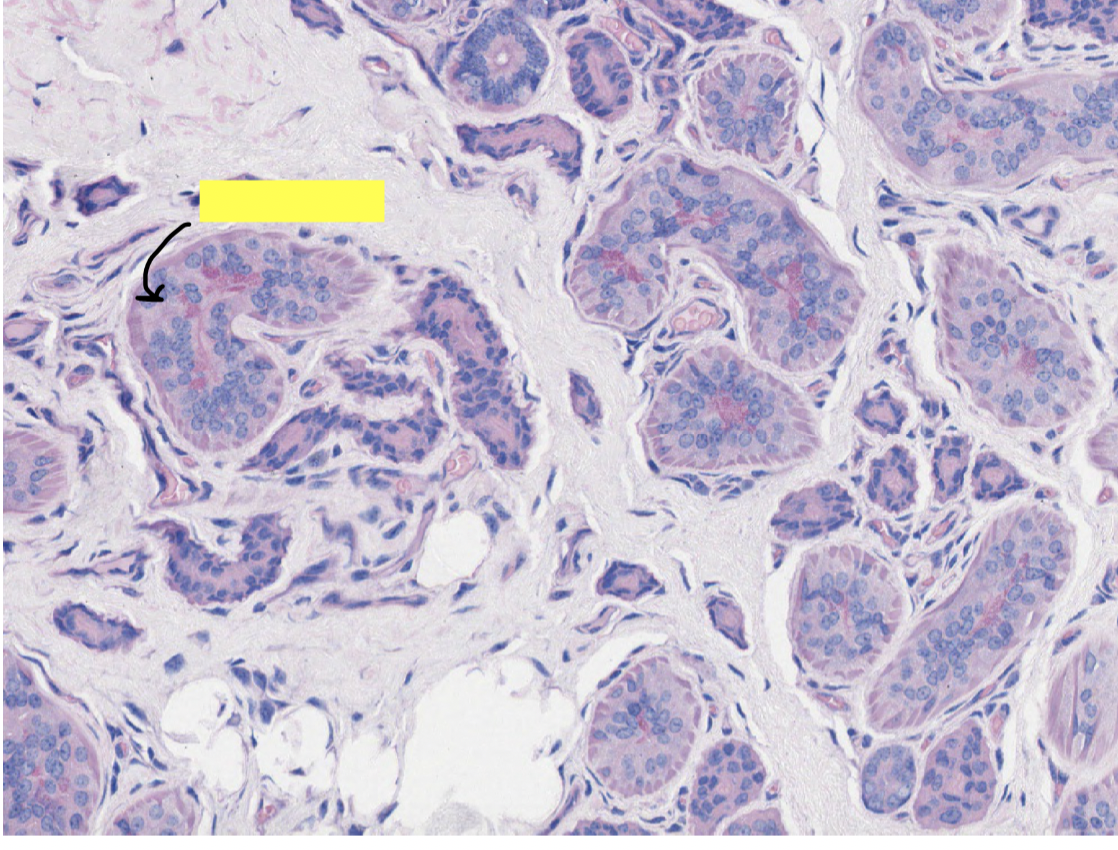

sweat gland ducts have what kind of epithelium

in what layer of the skin are sweat glands located

role